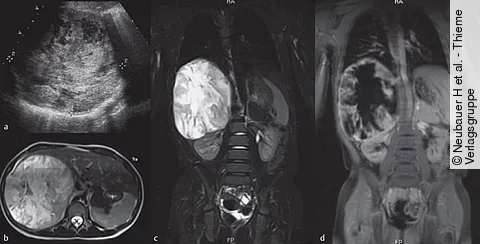

Quiz der WocheAuflösung: 7-Jährige mit Schulterschmerzen und Appetitminderung

Der vorliegende Fall unterstreicht eindrucksvoll die neuronale Verknüpfung der Viszera und ihrer Dermatome (Head-Zonen) auf spinaler Ebene.